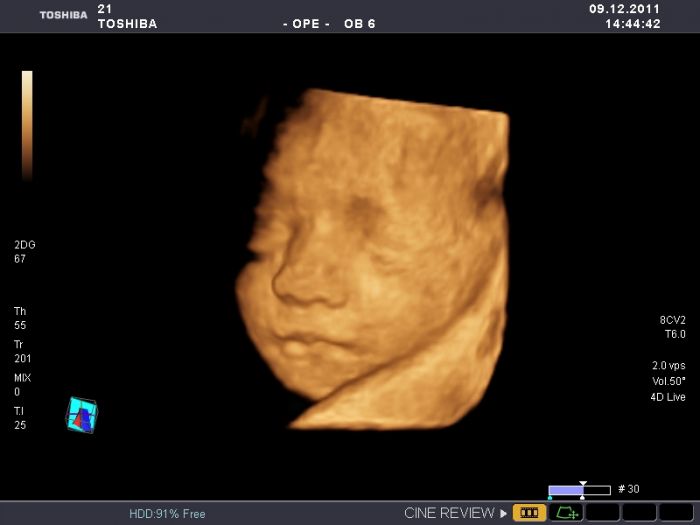

Ahoj holky,zdravím všechny takto po ránu.Skoro celou noc nespím,špatně se mi dýchá a tak jsem tu.. Do té nové diskuze miminka březen se nemůžu dostat i přesto,že jsem tu od samého začátku a jsem už i zaregistrovaná. neumíte mi s tím některá poradit čím to je? jinak čekáme holčičku a rodit budu někdy v půlce února.mám plánovaný císař,tak půjdu o něco dříve. už se nemuzu dockat,nejak uz to fyzicky ani psychicky nezvladam. pokusím se připojit foto mé maličké ve 27.tt ze 4D.Mějte se krásně.Káča

Kačí sice ti neporadím, ale musím ti pochválit malou

užasný fotečky. My bohužel na 4D nebyly tak ani nevíme jak mimčo bude vypadat.

Kačko, to je fakt nádherná fotečka...:) takhle by to mělo vypadat, ale myslim, že skoro nikomu se takovýhle fotečky nepoštěstí...:) jinak co se týče té diskuze, to budeš muset probrat s danielou a nebo rovnou s mitti...občas se asi objeví nějaké problémy...:( tak snad se to brzo vyřeší...:)